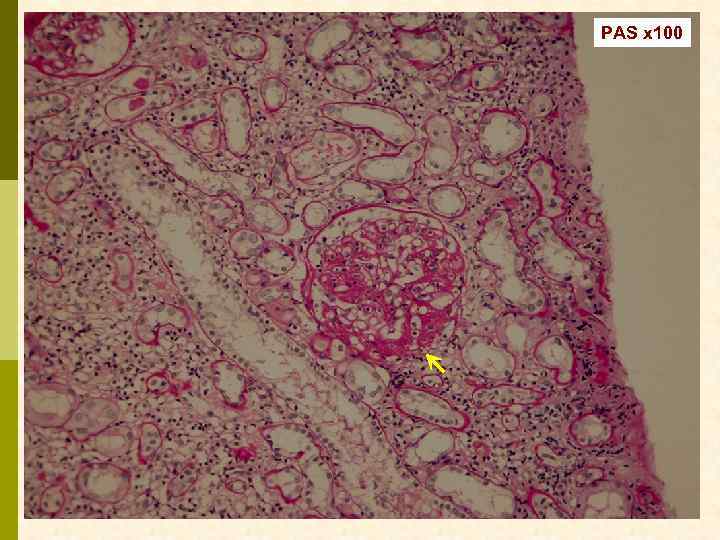

Б. Клинический случай № 21631 Александр К. , 1972 г. рожд. В 1999 г. выявлен гепатит С, в 2003 г. – ВИЧ. С июня 2006 г. – отеки, быстрое развитие анасарки. Почки по УЗИ 13 7 см. Протеинурия 9, 6 г/сут, креатинин 0, 19 мм/л, холестерин 18 мм/л. Обнаружен Ig. M-криоглобулин. 02. 11. 2006 - диагностическая нефробиопсия.

Иммунофлюоресцентное исследование: p Клубочки: Ig. G (2+), Ig. M (3+), C 3 (2+), kappa (3+), lambda (1 -2+) - диффузная, субэндотелиальная и интракапиллярная, крупно-гранулярная экспрессия; p Стенки артериол: C 3 (2+); p Цилиндры: Ig. G (2+), Ig. A (3+), Ig. M (2+), C 3 (3+), kappa (3+), lambda (2+); p Реабсорбированные белковые капли: kappa (3+).

Предварительное гистологическое заключение: p Мембрано-пролиферативный, HCV-ассоциированный, криоглобулинемический(? ) гломерулонефрит с полным склерозом 47% клубочков, сегментарным склерозом 22% клубочков и формированием полулуний в 15% клубочков; p диффузно-очаговый выраженный острый канальцевый некроз; p выраженный артерио-артериолосклероз. Примечание: Криоглобулинемическая природа поражения будет уточняться при ЭМ-исследовании.

Заключение p Мембрано-пролиферативный гломерулонефрит, криоглобулинемический, ВИЧ-ассоциированный, на фоне гепатита С

4 случая ВИЧ – 4 варианта морфологических феноменов ВИЧ-ассоциированной нефропатии p А – ФСГС, tip lesion p Б – МПГН криоглобулинемический p В – мембранозная нефропатия + ФСГС коллаптоподобный p Г – Ig. A нефропатия